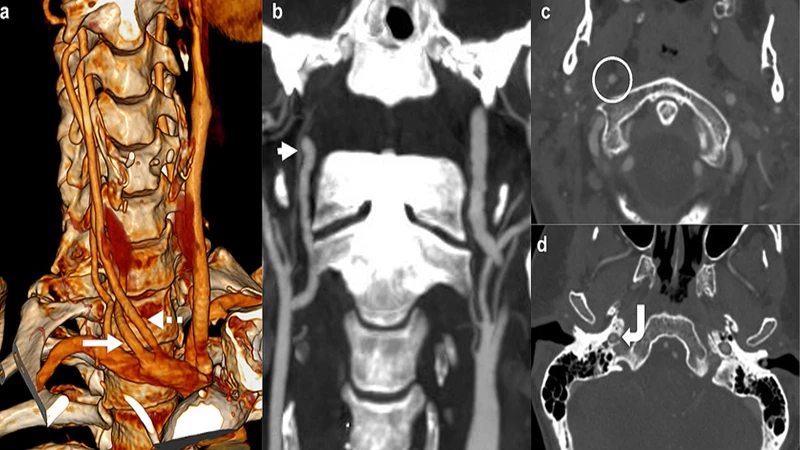

After the raw, thin-slice images are acquired, a technologist or radiologist uses specialized software to post-process the data. This involves digitally removing structures that are not needed (like bones and organs) to isolate the blood vessels. The software can then create stunning 3D reconstructions that can be rotated and viewed from any angle.

- CTA of the Head & Neck: Used to detect aneurysms, blockages (stenosis) in the carotid arteries that can lead to stroke, and vascular malformations.